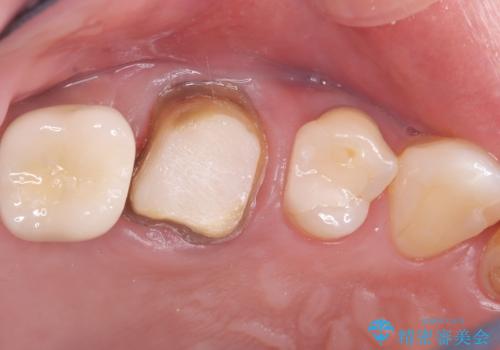

- 治療計画

- 患者様は、右側の奥歯でしっかり噛めないことを主訴に来院されました。診察の結果、右上6・右下6の根管治療が不十分で、感染のリスクがある状態と判断。これらの歯は再根管治療を行い、セラミッククラウンで補綴することにしました。また、右上7・右下7は欠損しており、噛み合わせを回復するためにインプラント治療を計画しました。

まず、右上6・右下6の根管治療を再度行い、根の状態をしっかり整えた上で、セラミッククラウンを装着しました。さらに、欠損していた右上7・右下7にはインプラントを埋入し、セラミッククラウンを装着。治療後は、「奥歯でしっかり噛めるようになり、不安なく食事ができるようになった」と患者様にも大変ご満足いただきました。